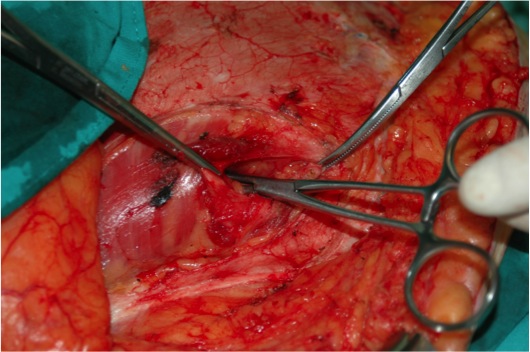

Imagen núm. 4: Apertura y exposición de la hernia.

Imagen núm. 5: Disección del saco herniario.